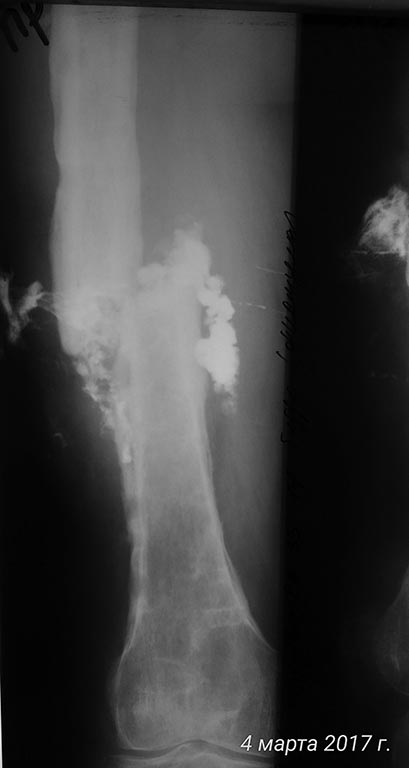

Дополняю рентген архив

Фистула

Прокомментирую:

самый первый снимок от 12.2016

Последние от 02.2017.

По рентгенограммам - тотальный остеомиелит бедренной кости. Для подтверждения можно сделать спиральную КТ. В Советское время выполнялись трепанации кости, долговременные активные промывные системы, эндостальное облучение кости лазером и т. п. Длительный постельный режим, огромный расход биологически активных препаратов, непрерывный врачебный уход... И это только для санации очага. Если нет возможности тотального эндопротезирования, то ампутация. И, так - делают!